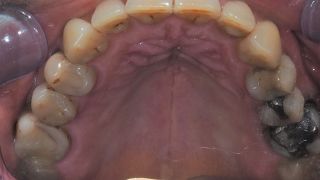

12a. 12b. 12c. 12d. Digital files after intra-oral scanning showing the gingival contouring for the prosthetic phase 4 months post implant placement.

12a

12b

12c

12d